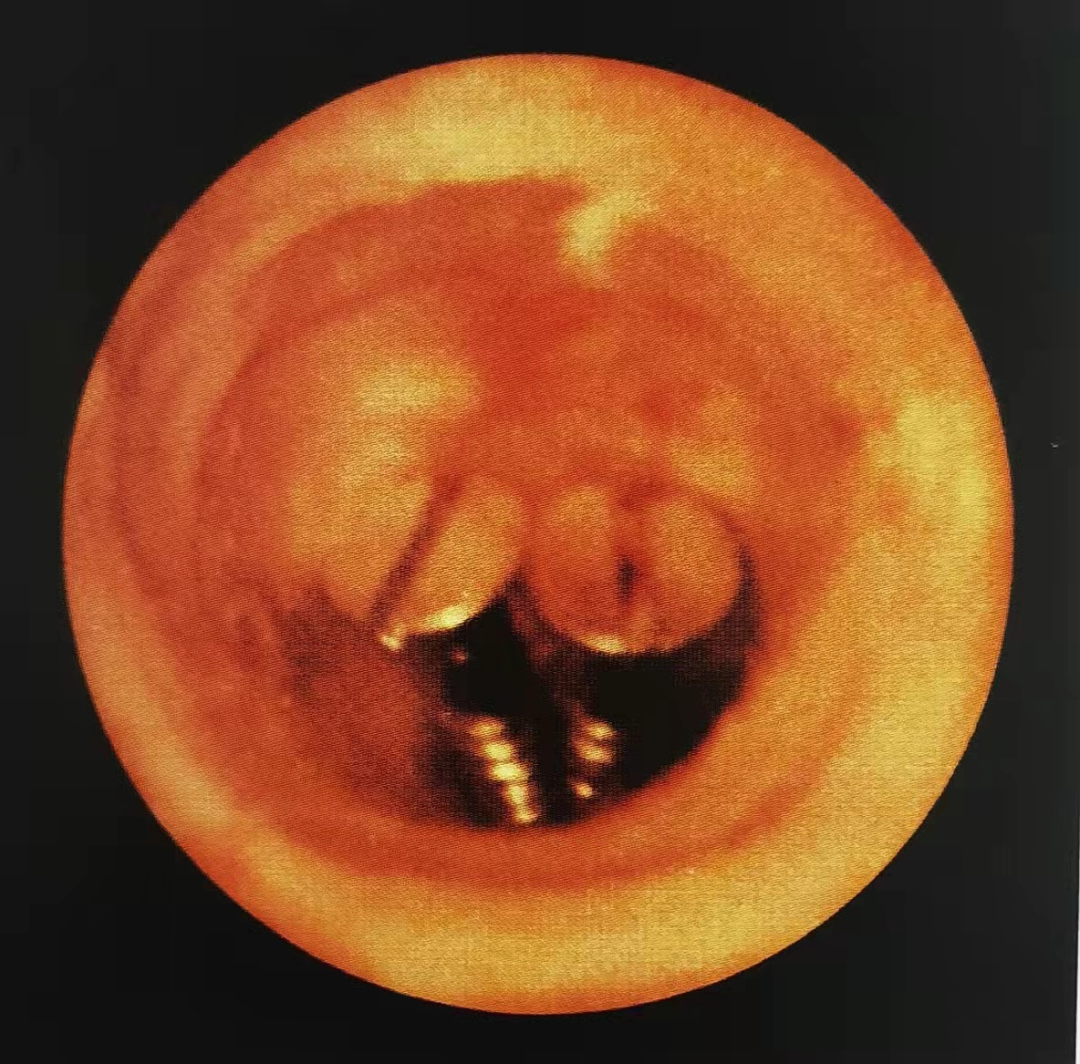

在麻醉下,我们的膀胱镜通过尿道进入膀胱,可以清楚的看到结节的真面目,而且我们可以利用活检钳,取出一小块肿瘤组织,送到病理科,通过病理检查我们可以准确的判断出结节的性质,这是最准确不过的了。

膀胱镜下我们看到的结节是这个样子的↓,是不是非常清晰!